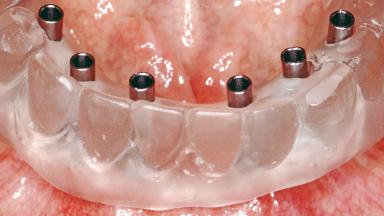

Conventional Loading of Six Implants in the Mandible and Final Restoration with a Full-Arch Metal-Ceramic FDP

A 68-year-old, completely edentulous male patient presented for evaluation and treatment options. He reported excellent general health and was taking no regular medication. He had been edentulous for approximately 12 years, having lost his teeth to periodontal disease and dental caries. The patient’s chief complaint was incompetent function. His secondary concerns included his appearance and the desire for a predictable outcome. He attributed his reduced functional capacity to his lower complete denture, which he described as poor. He was particularly concerned with the denture’s instability and poor fit. In general terms, he was satisfied with the maxillary complete prosthesis. The maxillary prosthesis was characterized by adequate retention, stability, and support, although the fit was considered less than ideal.

# of Implants 6

Type of Implants One-Piece

Prosthesis Type FDP

Defining Characteristics Fully edentulous lower jaw to be rehabilitated with an implant-borne fixed dental prosthesis

Retention Screw-retained, with 4 or more splinted implants Screw-retained, with 4 or more splinted implants